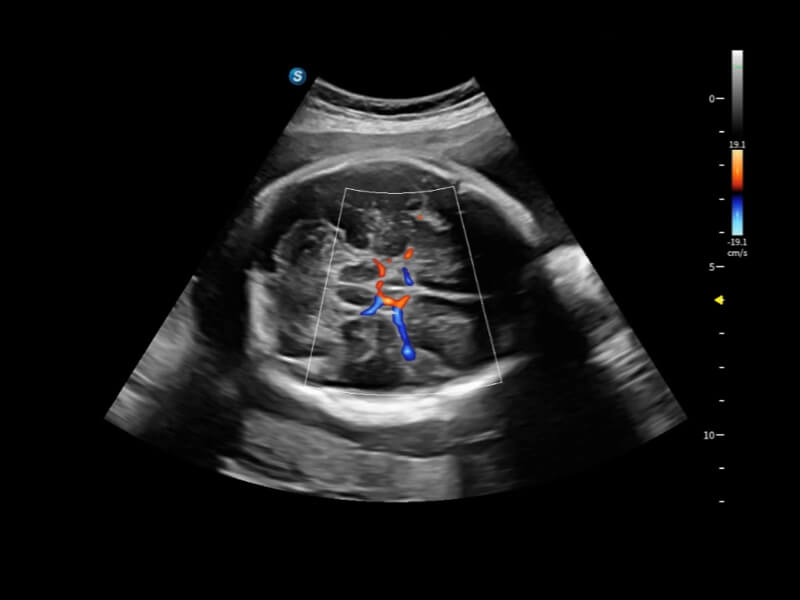

丰富的血流动力学检测技术,可在不同医疗场景中高效捕捉血流信号,助力临床诊疗。

在传统血流的基础上优化扫查和算法策略,能够更好的抑制组织信息,提炼红细胞运动信息,得到更高帧频,高灵敏度和分辨率的血流信号,还原更真实的血流动力学。

通过光照模型,使二维血流显示出立体的效果,增加血流的敏感性、成束性,减少外溢。可以和其他不同的血流技术联合使用,融合不同技术的优势。轻松应对微小血管,增强血流的立体效果,提升视觉敏感性。